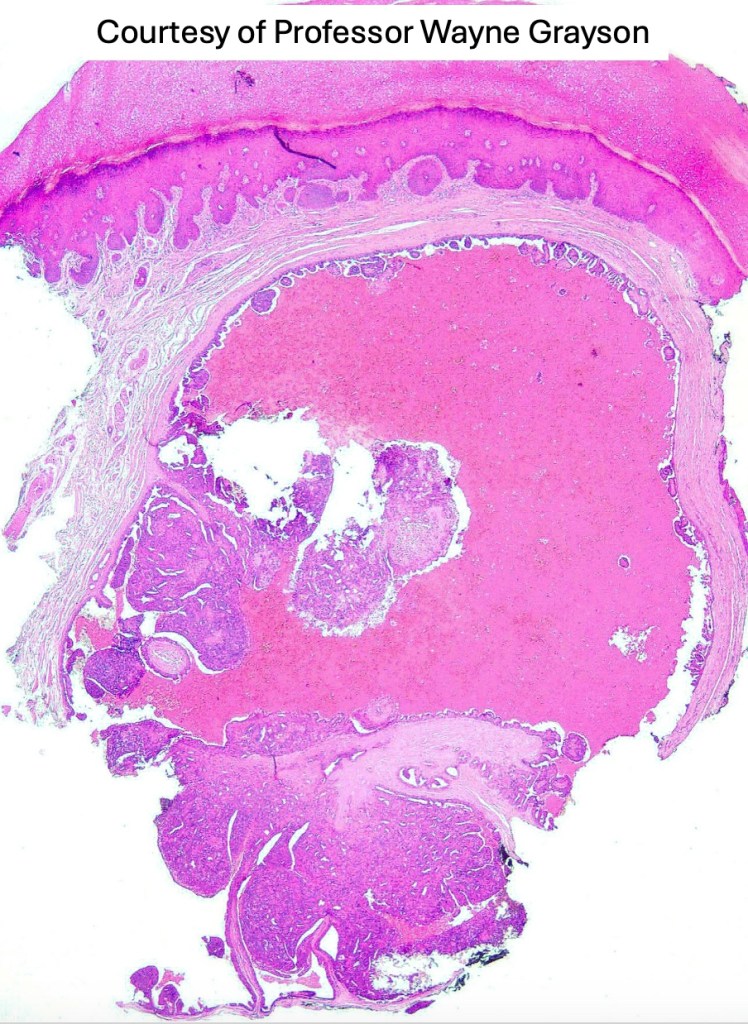

•Frequently circumscribed solid/cystic dermal nodule, infiltrative margin rare

•More advanced tumor can extend into subcutaneous fat, muscle & bone

•Papillary component (may include pseuopapillae & true papillae with a fibrovascular core)